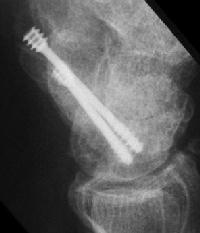

Case 8. Transscaphoid perilunate fracture dislocation...

Click for larger image

Two screws put in dorsally, LT ligament reinforced with a strip of extensor retinaculum left attached to the triquetrium and anchored into the lunate; temporary capitolunate pin.